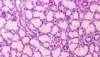

Identify the tissue.

Thyroid gland

Which gland?

Thyroid Gland